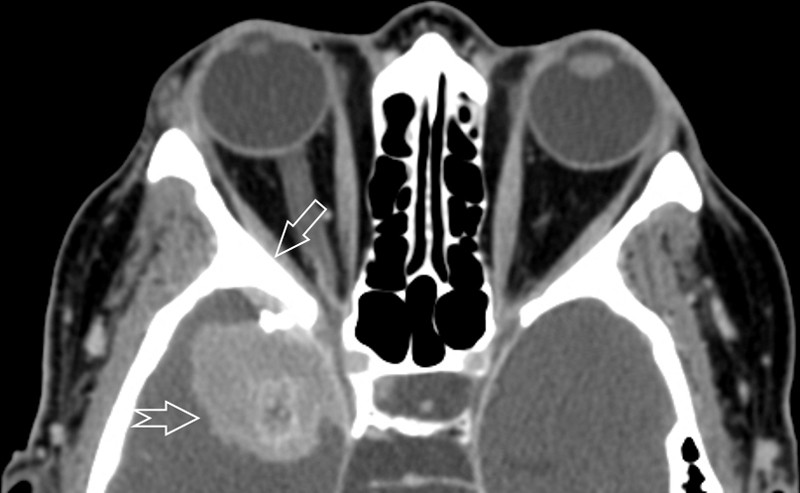

Fig. 1.

Axial computed tomography image without contrast, illustrating right sided sphenoid wing meningioma (notched arrow) measuring 5.4 cm × 4 cm × 5.3 cm (transverse × anterior-posterior × cranial – caudal). The bone along the right sphenoid wing, the anterior and posterior clinoid processes is hyperostotic (arrow). There was 1 cm of midline shift and vasogenic edema present in the right frontal and temporal lobes (not shown). The findings were consistent with meningioma and this was compared to the CT head from 10 years prior which had no evidence of lesion.